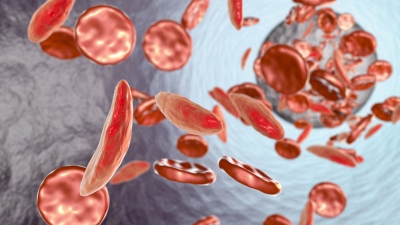

• η απώλεια αίματος από το ορθό

• η ανεξήγητη σιδηροπενική αναιμία

Περίπου 70-90% των περιπτώσεων έχουν διαγνωστεί μετά την έναρξη των συμπτωμάτων. Στην πορεία εξέλιξης των πολυπόδων σε καρκίνο απαιτούνται περίπου 8-14 έτη. Μόνο το 20% των περιπτώσεων θα δώσει συμπτώματα πριν τον καρκίνο. Αυτό και μόνο καταδεικνύει την απεριόριστη βοήθεια που προσφέρει η κολονοσκόπηση και η επακόλουθη πολυπεκτομή στην αντιμετώπιση του ορθοκολικού καρκίνου.